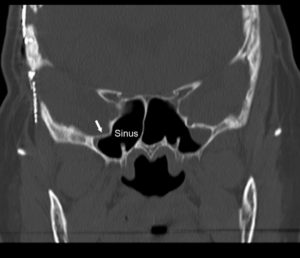

Cerebrospinal fluid (csf) is a fluid that cushions the brain Nasal csf leaks are caused by small, sometimes microscopic breaks in the barrier between the brain and roof of the sinuses A cerebrospinal fluid leak can cause symptoms like headaches, nasal drainage, and tinnitus If you have a persistent headache lasting a week or experience csf leaking from your ears or nose, see a healthcare provider

Csf leak may also be spontaneous, due to intracranial tumors, idiopathic intracranial hypertension (iih), or congenital skull defects. Csf rhinorrhea is a condition where cerebrospinal fluid (csf) leaks through the nose Normally cerebrospinal fluid is confined to the space around the brain and spinal cord Due to its close proximity to the sinus and nasal cavity, any opening will allow csf to leak into it and then drain out through the nose